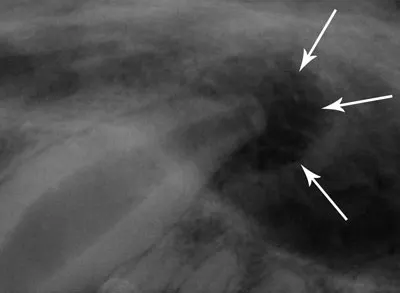

Figure 2: True periapical rarefaction; note that the lesion is more rounded and dark (arrows).

Featured Image